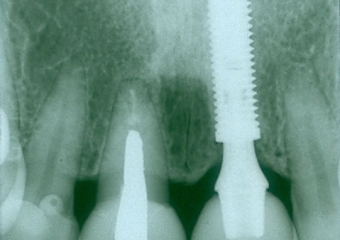

Raio X da prótese fixa em porcelana